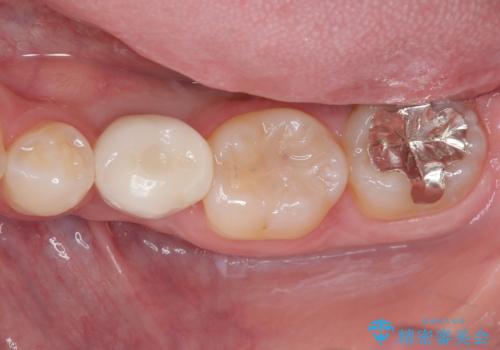

- 奥歯の虫歯を心配して来院した患者様です。

レントゲン写真から、以前治療した詰め物の下に虫歯があることがわかりました。

精度が高く、虫歯の再発リスクの低いゴールドインレーで治療を行うこととしました。